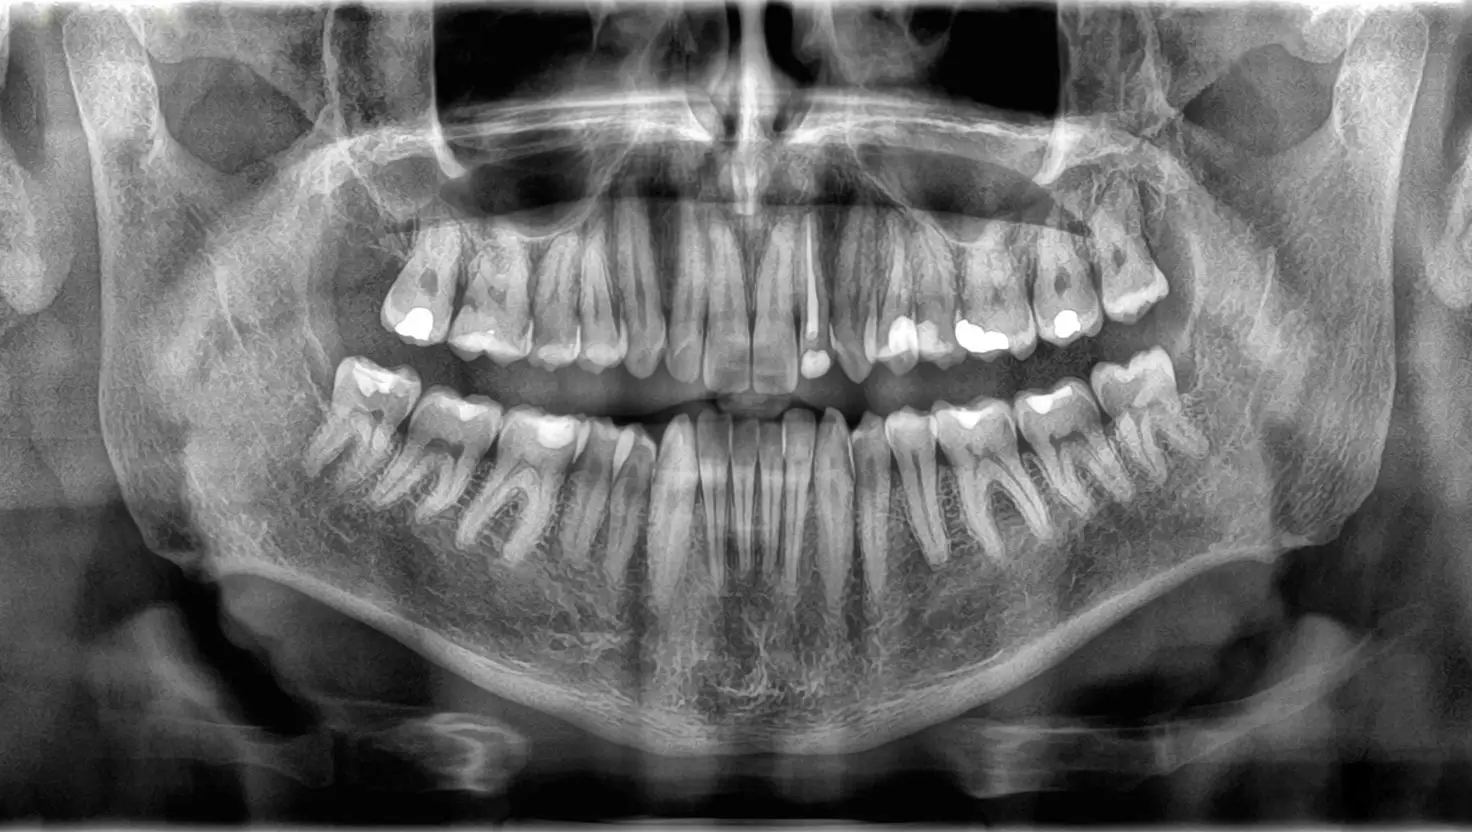

Other common side effects include swollen lymph nodes, racing heart and - according to dental experts - severe oral health issues.

GLP-1 drugs can reportedly stop you from producing enough saliva and eventually cause irreversible damage to your mouth.

“That combination can cause dry mouth, which increases the risk of cavities and gum disease,” he warned.

Gum disease, also known as periodontal disease, cannot be cured but it can be managed with appropriate treatment such as scaling, cleaning and pocket reduction surgery, detailed the Cleveland Clinic.

Dr Rajpal Anjali, a cosmetic dentist, said that common Ozempic side effects like acid reflux and vomiting can further erode your enamel further.

“Most users tolerate GLP-1 medications like Ozempic without serious oral health issues, but a subset experience notable side effects such as dry mouth, nausea, or vomiting, which can indirectly affect teeth and gums,” she explained.